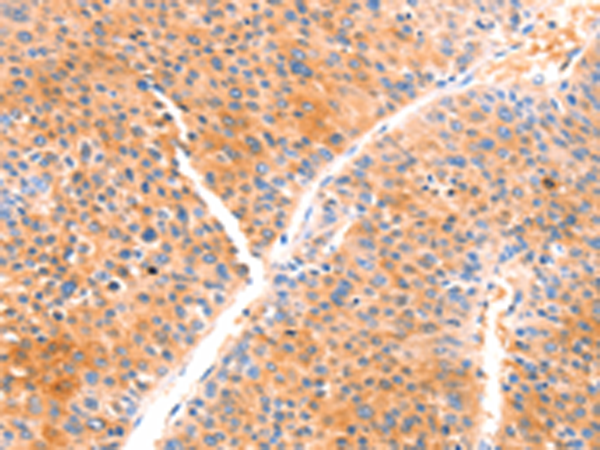

分类: 科研抗体货号: P11069别名: LKS; EPND; FESD; NR2A; GluN2A; NMDAR2A应用: IHC反应种属: Human, Mouse, Rat